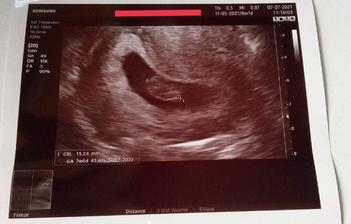

8. črc 2021